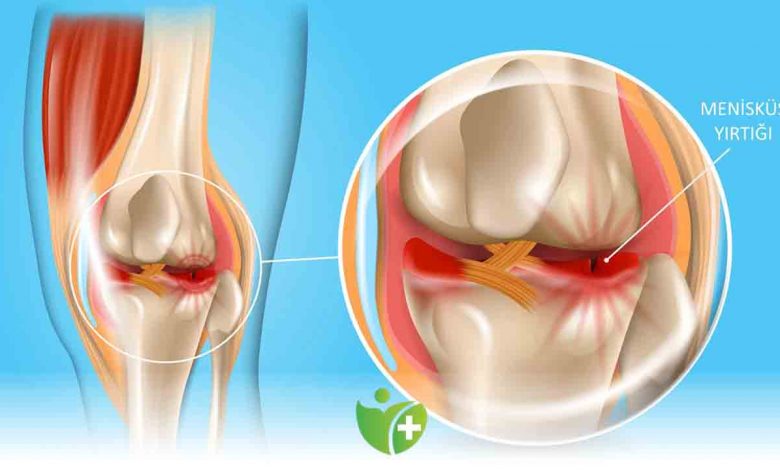

Menisküs, dizin içindeki kıkırdak dokusundan oluşan C şeklinde bir yapıdır. Her dizde iki adet menisküs bulunur: medial menisküs (diz iç kısmında) ve lateral menisküs (diz dış kısmında). Menisküsler, diz eklemindeki hareketleri destekler, dengeler, darbeleri emer ve stabilite sağlar.

Menisküs yırtılması, genellikle dizin ani bir dönme hareketi, bükülme, düşme veya dizin üzerine aşırı yüklenme sonucu oluşan bir diz yaralanmasıdır. Bu durumda, menisküs dokusu yırtılabilir veya zarar görür. Menisküs yırtılması genellikle ağrı, şişlik, dizde takılma hissi, kilitlenme hissi, sıvı birikimi gibi belirtilere yol açar.